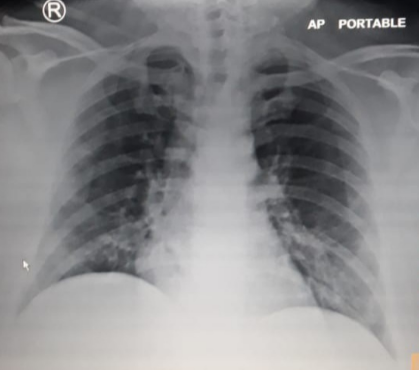

Figura 4. Radiografi portabël e pulmonit (COVID 19).

Krahasuar me CT, radiografia e pulmonit ka dozë më të ulët të rrezatimit. Mënyra më e mirë për të kuptuar dozën e rrezatimit nga një ekzaminim imazherik është të krahasohet kjo dozë me dozën e rrezatimit që marrim cdo ditë nga mjedisi që na rrethon.

Doza e rrezatimit të marr gjatë një CT pulmoni është e barabartë me 730 ditë të rrezatimit natyral, pra me rrezatimin natural që marrim në pëerditshmërinë tonë.

Doza e rrezatimit të marr gjatë një radiografie pulmoni është e barabartë me 2.5 ditë të rrezatimit natyral.